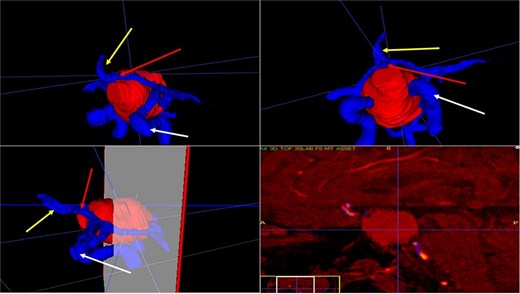

Contrast-enhanced T1 MRI of pituitary marcoadenoma. Multiplanar conventional geometric volumetry.

Manual planimetric volumetric segmentation. (A) Calculation of total tumor volume (red) and its relationship with the internal carotid artery (green). (B) Volumetry by zones. (C and D) Areas shown in sagittal and coronal planimetry.

| Geometric volumetry . | 3D volumetry . | Zone 1 Red (Intraspenoidal) . | Zone 2 Green (Intercarotid) . | Zone 3 Blue stronge (Supracarotid suprasellar) . | Zone 4 Yellow (Retrocarotid intraselar) . | Zone 5 Blue clear (Supraselar retrocarotid) . |

|---|---|---|---|---|---|---|

| 16 cubic centimeters | 21 cubic centimeters | 1.7 cubic centimeters | 3.7 cubic centimeters | 2.3 cubic centimeters | 9.7 cubic centimeters | 3.6 cubic centimeters |